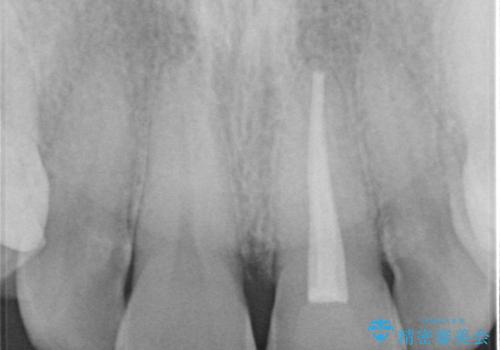

根管治療からのやり直しをした後、ジルコニアクラウンで色調の改善をしていきます。

- 左上1:根管治療(リトリートメント・前歯)/99,000円 ファイバーコア/22,000円 仮歯/11,000円 ジルコニアクラウン(スタンダード)/121,000円 合計253,000円費用は治療当時の料金となります